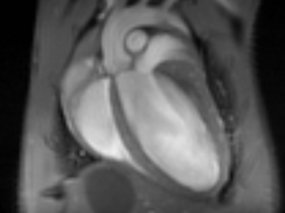

Recycling is also important in the human body. A disrupted protein recycling process can harm heart health.

January 22, 2025An enzyme called Ubiquitin-specific peptidase 5 is a key factor in protein quality in heart muscle cells.